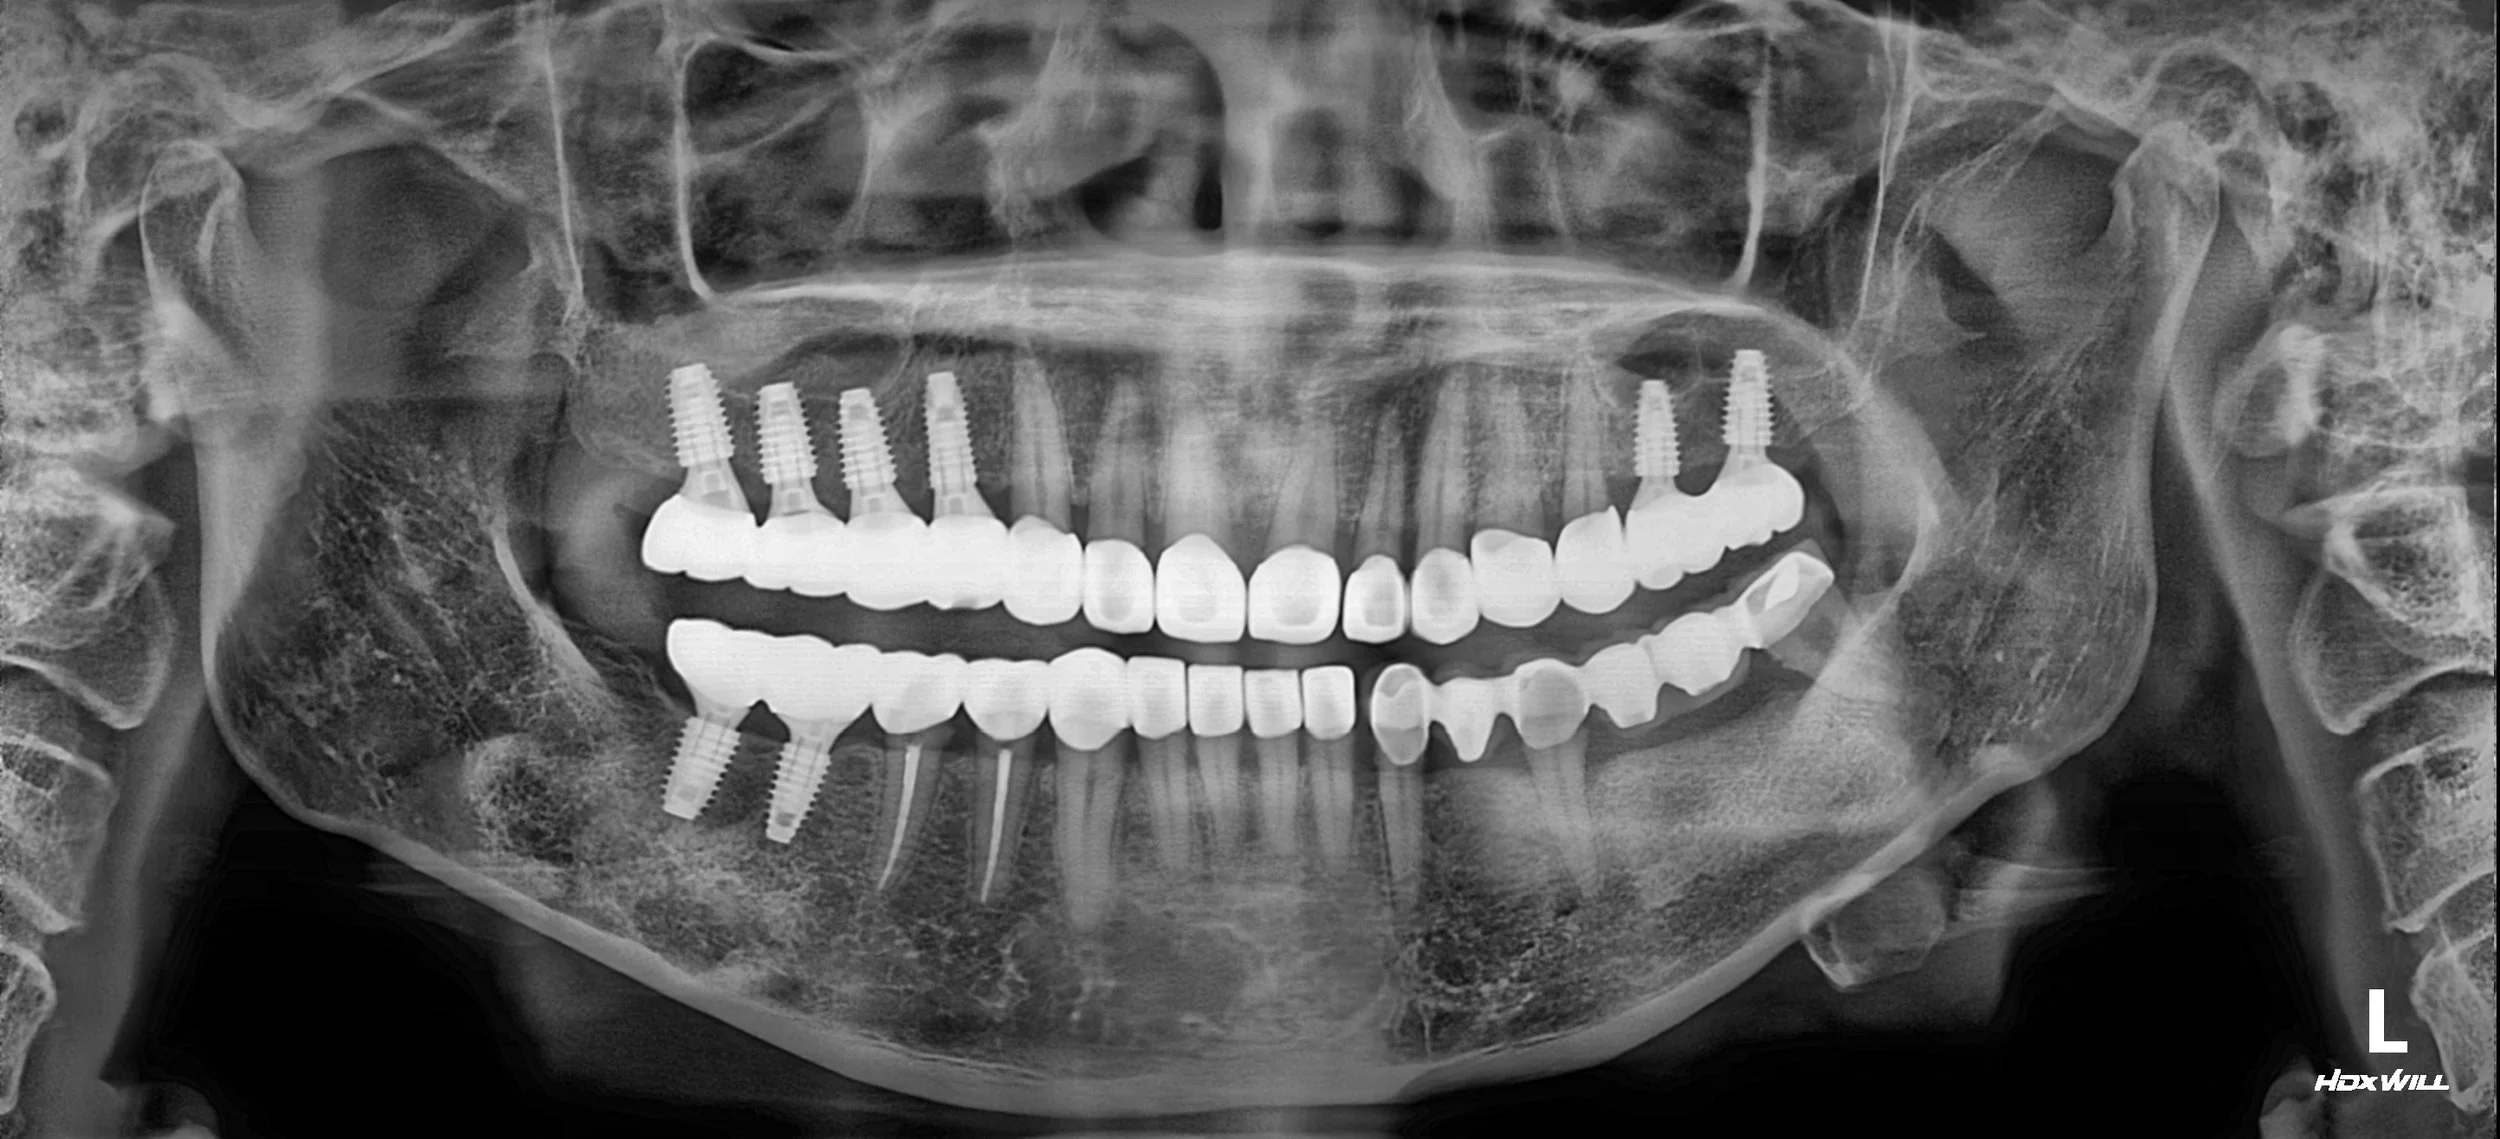

OPG - AFTER

A prosthetic-driven occlusal rehabilitation was performed with careful vertical dimension adjustment.

Anterior restorative space was secured to address aesthetic concerns,

while the occlusal scheme was redesigned to allow force distribution across the arch.

By integrating the existing bridge into a balanced occlusal framework,

long-term maintenance of both old and new restorations was prioritised.